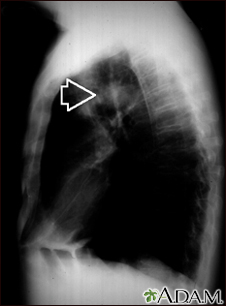

Pulmonary mass - side view chest x-rayBackPulmonary mass - side view chest x-rayThis individual has a mass in the upper part of the lung. Although the cause of the mass can be suspected, based on this person's history, there are many diseases that can produce lung lesions. E-mail FormEmail ResultsName:Email address:Recipients Name:Recipients address:Message: